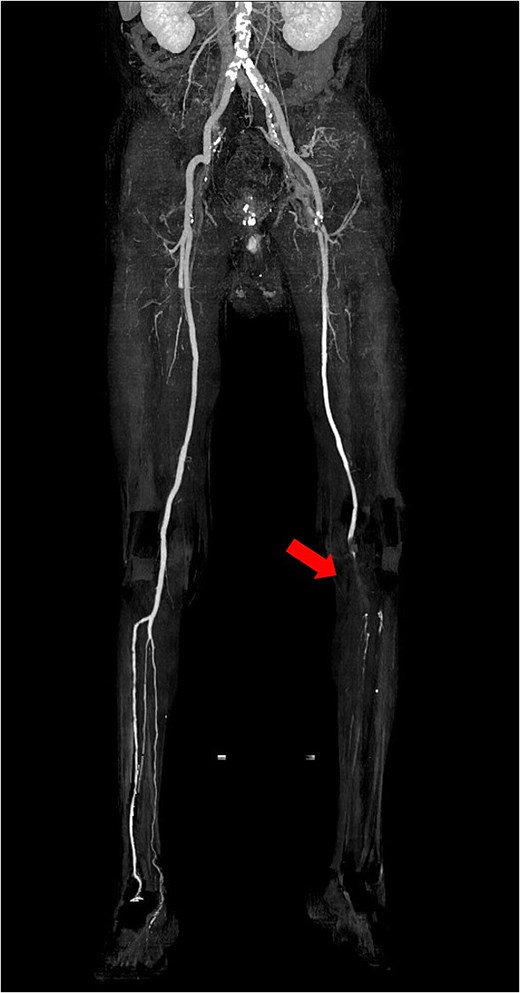

The patient was a 78-year-old man who had been hospitalized at a prior institution for Tolosa-Hunt syndrome, a rare inflammatory condition causing orbital pain. He had undergone steroid pulse therapy and was maintained on oral prednisolone (40 mg daily). He was also receiving medical treatment for diabetes mellitus, with an HbA1c level of 7.9%. The patient presented with complaints of left leg discomfort and weakness. Contrast-enhanced CT revealed poor perfusion distal to the left common iliac artery, leading to a diagnosis of ALI. He was subsequently transferred to our surgical department for further evaluation and treatment. On arrival, physical examination revealed coldness in the left lower limb, with absent palpable pulses in the dorsalis pedis and posterior tibial arteries. Doppler ultrasonography confirmed the absence of arterial flow in the left lower extremity, consistent with critical ischemia. The patient's electrocardiogram showed sinus rhythm. A review of CT imaging showed thrombotic occlusion extending from the left common femoral artery (CFA) to the superficial femoral artery, with poor perfusion distal to the popliteal artery (Video 1) (Fig. 1). Additionally, a filling defect was identified in the distal aortic arch, consistent with a thrombus (Fig. 2a). The thrombus appeared pedunculated and was attached to the lesser curvature of the descending thoracic aorta distal to the left subclavian artery. It was considered highly mobile, posing a significant risk of embolization. No evidence of intracardiac thrombi was observed, and the DTAT was identified as the likely embolic source responsible for the ALI. Given the urgency of salvaging the ischemic limb, thrombus retrieval was prioritized, while simultaneous management of the embolic source was deemed equally critical to prevent recurrence. Open surgery was considered high-risk due to the patient’s age, diabetes, and chronic steroid use. As a less invasive alternative, we opted for TEVAR to immobilize the floating thrombus. During the procedure, bilateral CFAs were surgically exposed to provide access and enable immediate removal of the embolic source if needed. A transesophageal echocardiogram (TEE) revealed a highly mobile intra-aortic thrombus (Video 2). A 26× 26 × 150 mm stent graft (Valiant Captivia Thoracic Stent Graft; Medtronic, Santa Rosa, CA, USA) was deployed just distal to the left subclavian artery under fluoroscopic guidance. Real-time TEE guidance ensured continuous monitoring of the floating thrombus and confirmed no embolization during intravascular manipulation. Following stent graft deployment, thrombus retrieval was performed via the left CFA using a 4-Fr Fogarty catheter (Fogarty Fortis arterial embolectomy catheter; Edwards Lifesciences, Irvine, CA, USA), successfully retrieving fibrin thrombi. Intraoperative angiography demonstrated restored blood flow in the lower extremity, with improved perfusion extending to the foot. Pulses in the dorsalis pedis and posterior tibial arteries were palpably restored bilaterally. The patient was extubated in the operating room and progressed without any findings suggestive of intestinal or lower extremity ischemia. Postoperative CT confirmed successful exclusion of the aortic thrombus (Fig. 2b) and restoration of adequate lower limb perfusion (Fig. 3). The patient was initiated on oral anticoagulation therapy with edoxaban 30 mg to prevent future thrombus formation and experienced an uneventful recovery. This patient has remained free of recurrent embolic events and has shown stable progress post-procedure.

Preoperative 3D reconstructed contrast-enhanced CT. No contrast effect is seen in the blood flow of the lower leg.

Postoperative 3D reconstructed contrast-enhanced CT. The contrast effect on lower limb blood flow is good.